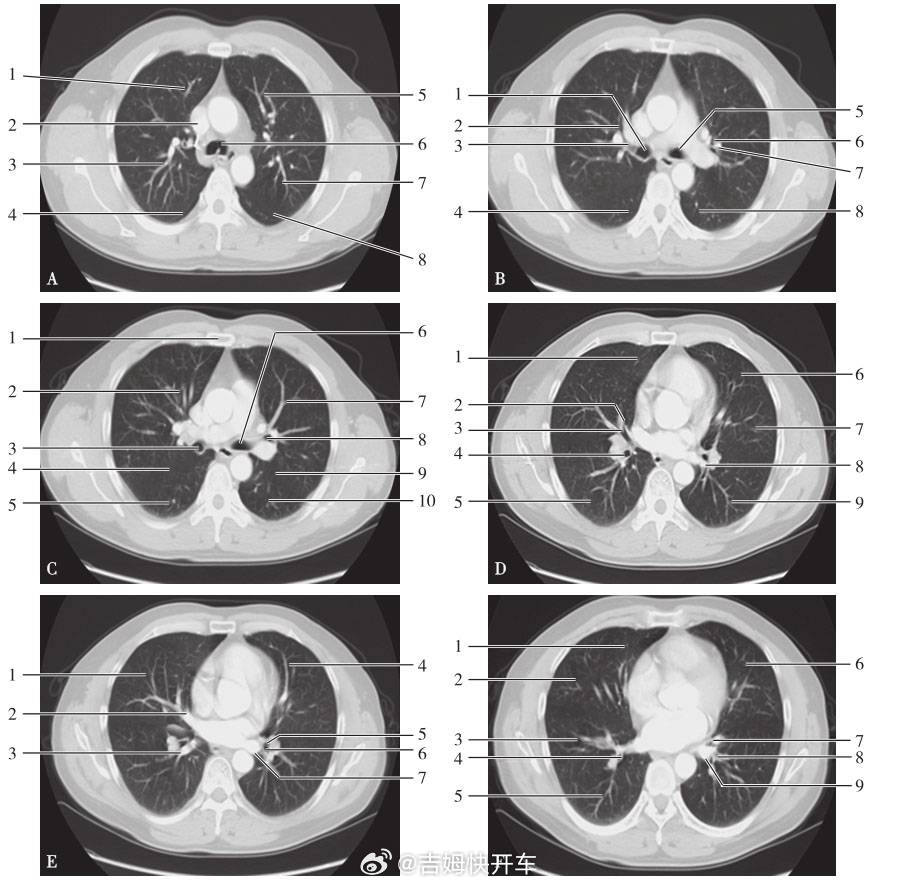

原来香蕉有辐射日常生活里能接触到的,去医院拍片是辐射最大的,其中胸部CT的辐射量是最高档那一类的。

一次胸部CT等于飞700小时飞机的辐射量,差不多是拍280次口腔CT,也就是吃了70000根香蕉的辐射量,哈哈哈哈这什么离谱的换算